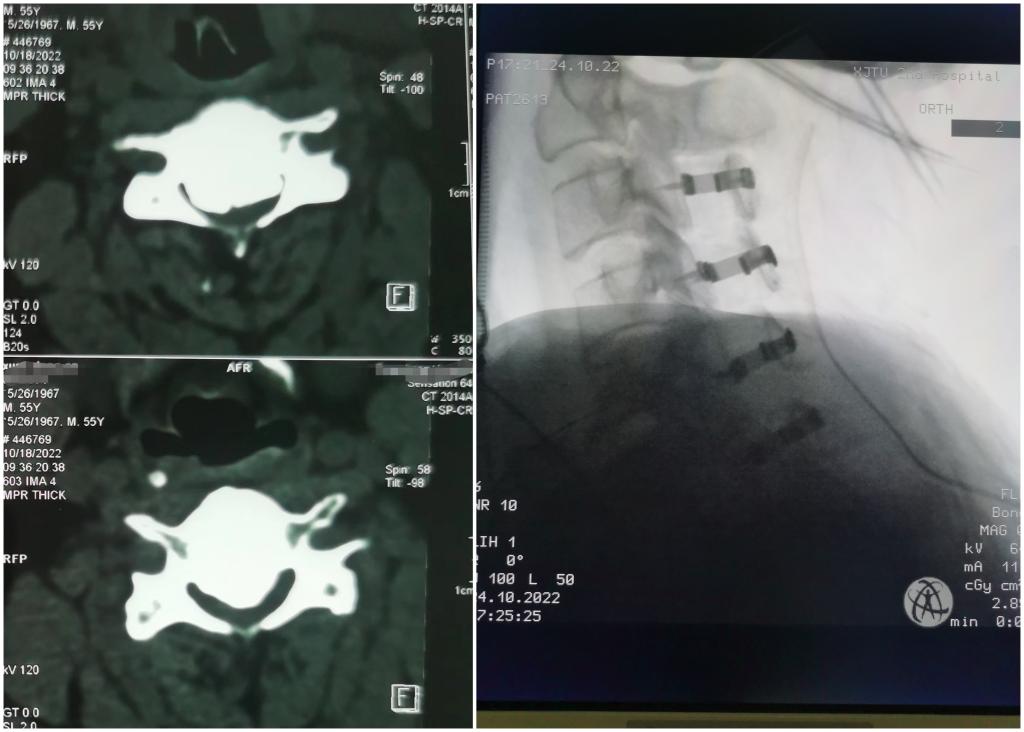

患者华XX(化名),突发颈部以下感觉麻木,不能正常行走,双手不能活动。经检查发现患者后纵韧带骨化严重,椎管内骨化占位已达到近80%,脊髓已经压迫到了“细片”状程度,严重威胁脊髓神经功能,随时有发生高位截瘫的可能。得知我院骨三科脊柱外科团队在高难度颈椎手术方面具有丰富诊疗经验,由外院转至我院骨三科。

骨三科主任张纯教授团队仔细分析患者临床资料,考虑到患者年轻、压迫极其危险等特点,需要手术治疗,但是面临患者脊髓压迫已到临界点,随时存在瘫痪可能,手术风险极大。全面评估后,决定先行后路脊柱单开门减压手术方式,二期颈椎前路椎体次全切除减压植骨融合内固定手术。

2022年10月24日,由张纯主任医师主刀,王伟卓副主任医师、刘若西主治医生配合,李伟教授、张鹏、代志明团队麻醉,王芳术中肌电图监测。手术如期开展,但麻醉后,肌电图报告患者运动体感诱发电位波幅非常微弱,给神经监测带来极大难度,增加了手术难度。为了患者获得救治,张主任团队凭借多年复杂颈椎手术经验,迎难而上,精准轻柔操作,当椎板打开、脊髓减压后,患者肌电图波幅逐渐出现,大家顿感轻松,如释重负,手术持续约三个小时,顺利完成。